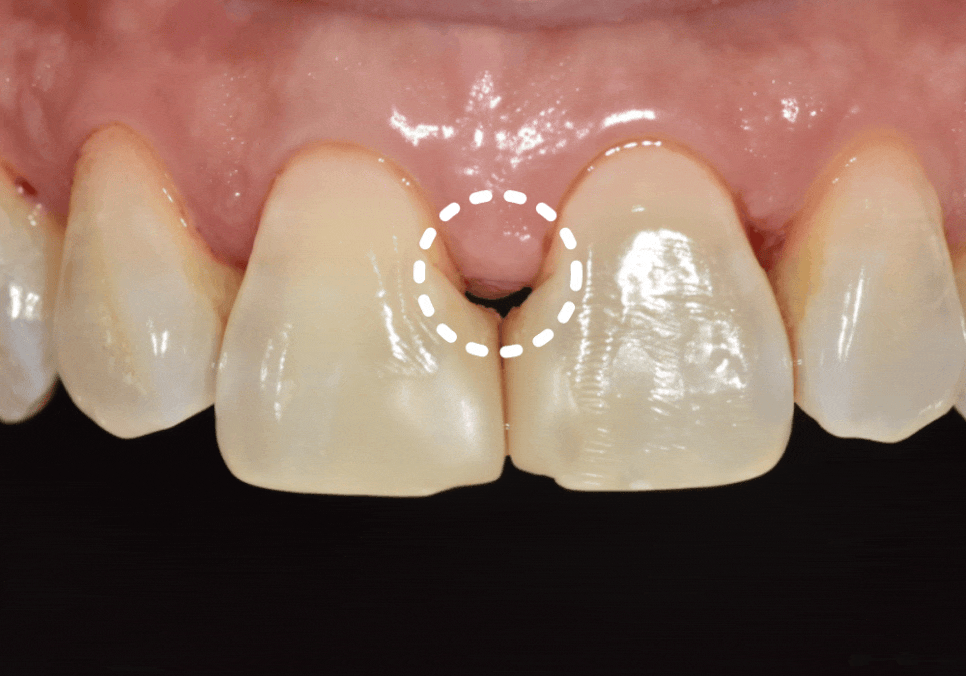

나이가 들수록 잇몸은

자연스럽게 조금씩 내려가게 되는데,

고덕동 치과 누런 이, 앞니 사이 틈, 잘못된 관리 때문일까?

이 과정에서

잇몸과 레진으로 막아두었던 경계 부위 사이에

미세한 틈이 생기게 됩니다.

잇몸이 내려가면서 치아 사이 공간이

삼각형 모양으로 검게 보이는 현상을

"블랙 트라이앵글(Black triangle)"이라고 합니다.

실제로 1년 전 초진 사진과

최근 사진을 비교해 보니,

잇몸 퇴축이 눈에 띄게 진행되면서

블랙 트라이앵글의 크기가

이전보다 확연히 커진 상태였습니다.